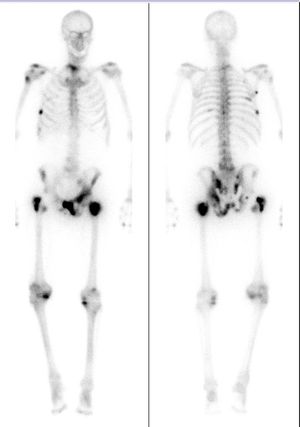

생검에서 암세포가 발견되면, 조영 CT를 통해 림프절 전이 유무, 정낭 침윤 등 전립선 피막 외 암 침윤 여부를 검사하지만, CT를 이용한 정낭·피막 외 침윤, 림프절 전이의 진단능은 낮다. 전립선암은 비교적 뼈로 전이되기 쉬우므로, 핵의학 검사인 골 스캔으로 골 전이 유무를 평가해야 한다. 또한, MRI를 시행하는 경우도 적지 않다. 이전에는 PSA 고농도 증례에 대해 루틴으로 MRI 검사를 시행하는 것을 의문시하는 의견도 있었지만, 최근에는 자력 강도가 높은 MRI(3.0테슬라 MRI)나 경직장 MRI를 사용함으로써 보다 정확한 영상 진단이 가능해지고 있다.

- 임상적 재발: CT, MRI, 골 스캔 등 영상 검사나 직장 수지 검사로 확인되는 재발로, 전립선 국소 병소, 림프절, 골 전이 등이 관찰된다.